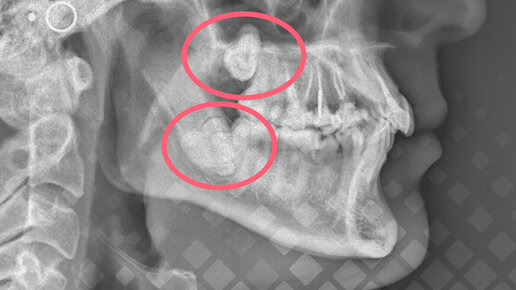

«Удалила зуб мудрости и мне разнесли пол челюсти». Больно ли на самом деле удалять зубы мудрости?

Да, такие истории, увы, не редкость. Но на самом деле удаление зубов мудрости – лишь в половине случаев действительно сложная процедура. Прорезываются самые дальние зубы поздно и в процессе доставляют массу неудобств. Из-за этого многие пациенты боятся их удалять, и планово, и по показаниям, когда уже трудно терпеть боль. Но спешим заверить, при всей сложности процедуры для пациентов, для врача она – самая рядовая. Сегодня удалять зубы мудрости не больно, а лишь немного страшно 😄. Расскажем, как...